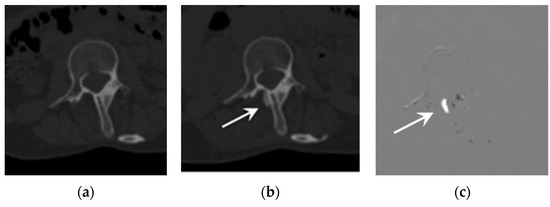

Representative cases are shown in Figure 1 and Figure 2. Both cases showed better detectability of emerging or growing ossifications when using TS compared to when not using TS.

Figure 1.

Example of an emerging lesion. CT images of a 25-year-old FOP patient: (a) previous CT image, (b) current CT image, and (c) TS (subtraction) image. The emerging lesion adjacent to the thoracic spine (arrow) is difficult to detect on the current CT image, but is clearly visible in the TS image.

In addition to the improvement in sensitivity, the number of false positives per case when using TS tended to be higher than when not using TS for three out of the four interpreters. This was partially due to the misregistrations of TS in some cases (Figure 2 and [12]). It is well known that the image quality of TS images significantly affect diagnostic performance [17], and a further improvement in the image registration algorithm would be desirable for more accurate diagnosis.